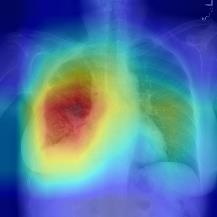

Thoracic disease detection from chest radiographs using deep learning methods has been an active area of research in the last decade. Most previous methods attempt to focus on the diseased organs of the image by identifying spatial regions responsible for significant contributions to the model's prediction. In contrast, expert radiologists first locate the prominent anatomical structures before determining if those regions are anomalous. Therefore, integrating anatomical knowledge within deep learning models could bring substantial improvement in automatic disease classification. This work proposes an anatomy-aware attention-based architecture named Anatomy X-Net, that prioritizes the spatial features guided by the pre-identified anatomy regions. We leverage a semi-supervised learning method using the JSRT dataset containing organ-level annotation to obtain the anatomical segmentation masks (for lungs and heart) for the NIH and CheXpert datasets. The proposed Anatomy X-Net uses the pre-trained DenseNet-121 as the backbone network with two corresponding structured modules, the Anatomy Aware Attention (AAA) and Probabilistic Weighted Average Pooling (PWAP), in a cohesive framework for anatomical attention learning. Our proposed method sets new state-of-the-art performance on the official NIH test set with an AUC score of 0.8439, proving the efficacy of utilizing the anatomy segmentation knowledge to improve the thoracic disease classification. Furthermore, the Anatomy X-Net yields an averaged AUC of 0.9020 on the Stanford CheXpert dataset, improving on existing methods that demonstrate the generalizability of the proposed framework.